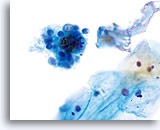

Chronic Follicular Cervicitis

The presence of lymphocytes accompanied by tingible body macrophages may indicate a chronic inflammatory condition or the rupturing of a lymph follicle during sample collection. On the ThinPrep slide the lymphocytes from chronic follicular cervicitis will generally appear in small clusters grouped together. The presence of tingible body macrophages aid in the diagnosis.